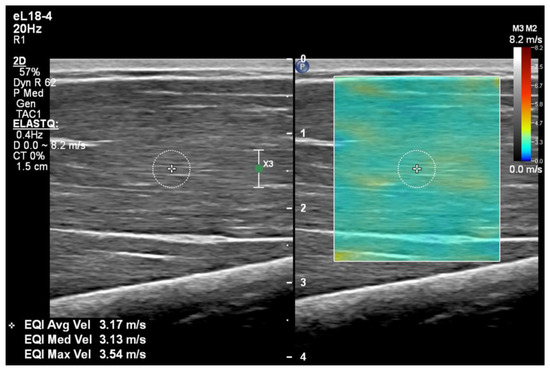

The participants were asked to relax and not move or contract their muscles during the scan. If the muscle was activated in this way, the SWE would display higher colour maps almost instantly. The participant would then be reminded to relax, and the measurement would be re-taken a few seconds later. Once the elastogram was stable, the image was frozen and a 5 mm calliper was placed in the middle of the elastogram, avoiding any fascia, nerves, or vessels (Figure 2). The ultrasound machine calculates the velocity of the Shear Wave within the calliper and returns a measurement in m/s. Five measurements were taken in each muscle belly, at each elbow position, in each arm.

Figure 2. The elastogram of the left arm long head of the biceps brachii at the 60° elbow angle. The colour box is superimposed over the B-mode, and a 5 mm calliper has been placed within the muscle belly, which returned an average velocity of 3.17 m/s. The green dot represents the depth of the focal zone, which is aligned with the calliper.